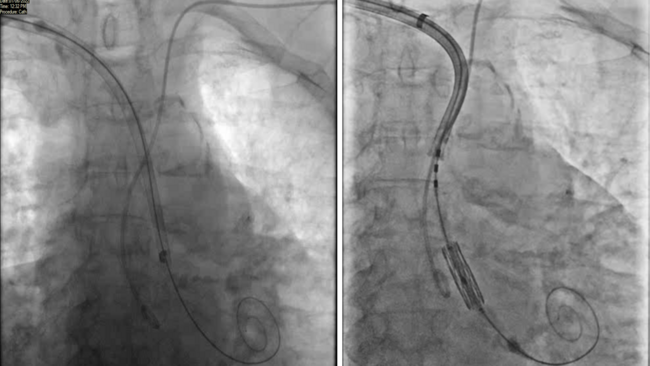

We prepared for right transaxillary TAVI under anesthetic sedation. A Vygon arterial line was placed in the right radial artery and 5 Fr radial sheath was inserted in the left radial for secondary access. Under ultrasound guidance, a 6-Fr access was inserted into the right axillary artery. A ProGlide was deployed for pre-closure. A 6-Fr sheath was progressively up-sized to allow insertion of a 16-Fr eSheath. The initial alignment of the S3 valve was not co-axial with the aortic annulus (Figure 6A). Using the retroflex of the ES commander system, the 29 mm S3 Ultra valve was positioned to the greater curvature of aorta allowing co-axial alignment (Figure 6B). A 29 mm S3 Ultra valve was deployed in a satisfactory position (Figure 6C). Initially there was mild to moderate aortic regurgitation, but this was obliterated with a further 1 ml of contrast. Right axillary artery closure was achieved with an 8-Fr Angio-Seal vascular closure and a ProGlide vascular closure system. There were no complications, and the patient went home the next day.